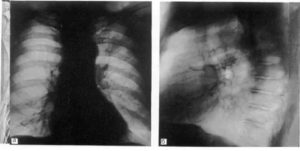

На рентгенограмме грудной клетки в прямой проекции при релаксации рентгенограммы определяется ее контур, расположенный гораздо выше обычного, в боковой проекции контур диафрагмы образует с грудной стенкой прямой угол.

Сразу же под куполом диафрагмы можно увидеть желудок, а также заполненный газом селезеночный угол ободочной кишки.

Схематичное изображение релаксации диафрагмы на рентгеновских снимках в условиях диагностического пневмоперитонеума (слева): цифрой 1 обозначен свободный газ в брюшной полости, цифрой 2 – купол диафрагмы («пограничная линия»), 3 – желудок и газовый пузырь желудка, 4 – толстая кишка, 5 – тень левого желудочка сердца. Справа – грыжа диафрагмы, которая может симулировать релаксацию левого купола, диагностический пневмоперитонеум: обозначения те же

Рентгеновские признаки релаксации диафрагмы с левой стороны: определяется высокое стояние левого купола диафрагмы, под ним отчетливо виден газовый пузырь желудка, а также петли толстого кишечника